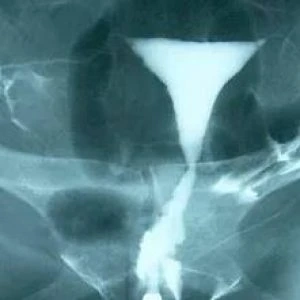

Η κλασική σαλπιγγογραφία (ή υστεροσαλπιγγογραφία) είναι μια μη επεμβατική μέθοδος απεικόνισης των σαλπίγγων που χρησιμοποιείται σχεδόν για έναν αιώνα και γίνεται σε ακτινολογικό εργαστήριο.

Η διαδικασία της αξιολόγησης ξεκινά με την τοποθέτηση (με ειδικό καθετήρα) ενός σκιαστικού υγρού μέσα στη μήτρα. Στη συνέχεια, το σκιαστικό προωθείται με πίεση προς τις σάλπιγγες και βγαίνει από αυτές στην περιοχή της πυέλου της γυναίκας. Κατά τη διάρκεια αυτής της προώθησης του σκιαστικού, λαμβάνονται επαναλαμβανόμενες ακτινογραφίες της πυέλου.